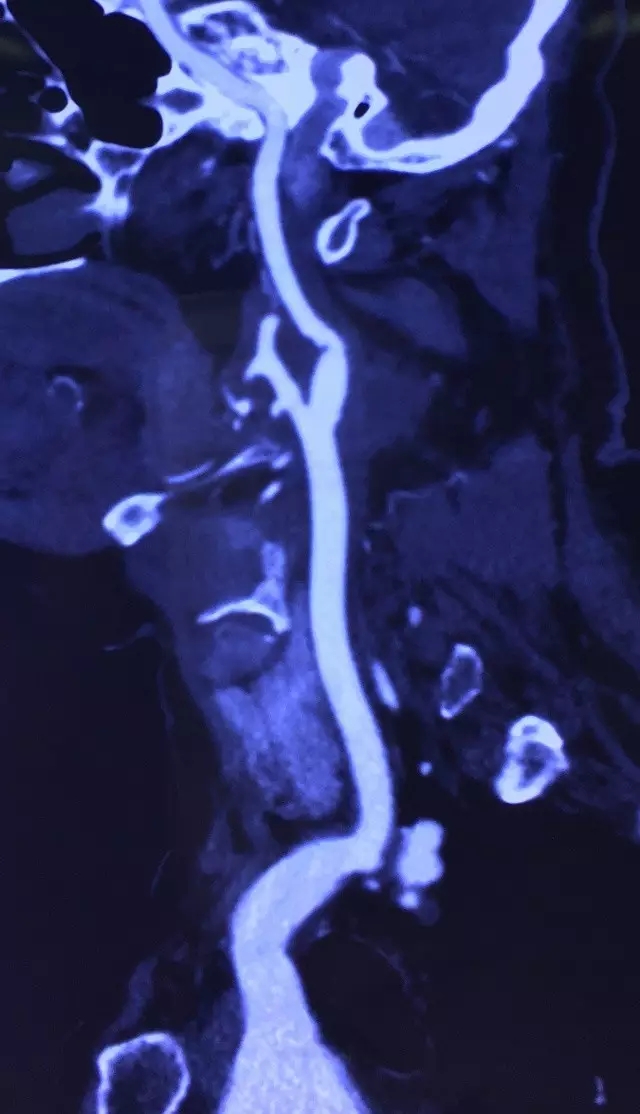

入院后医院副院长、血管外科专家王兵教授及崔文军副主任医师高度重视,亲自查看患者,仔细查体,并在右颈部触到一搏动性包块,遂指示主管医师吴斐积极完善颈动脉CTA检查。很快检查结果回示:复杂右颈内动脉瘤,瘤体位置高,颈内动脉迂曲严重(图1)。原来是瘤体内血栓脱落导致脑梗塞的发生,真相大白,元凶终被发现。而如何拆除这枚定时炸弹却是个异常棘手问题。

图一

简单颈内动脉瘤常可通过微创腔内治疗,恢复快,操作简单,也是目前血管外科医师最常选用的方法。但此患者颈内动脉扭曲严重,瘤体大,位置高,接近颅底,瘤体内血栓充填,微创腔内治疗常会造成无法达到病灶位置及血栓脱落导致大面积脑梗塞等严重后果。